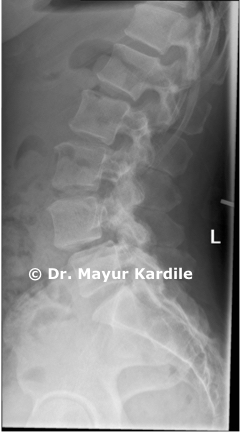

Case Images